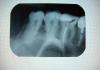

Quad Опубликовано 16 февраля, 2008 Поделиться Опубликовано 16 февраля, 2008 (изменено) Здравствуйте, 1) Скажите, правильно ли запломбированы каналы в 6? Врач,делающий рентген,сказал,что материал немного вышел. Если,да,то нужно ли перепломбировать?6 под временной пломбой уже 3 неделю. Тк после пломбировки каналов была воспалена связка зуба(как мне объяснили) и штифт ставить нельзя было. Сейчас зуб болит(вернее его половина) при надавливании на него с внутренней стороны,а с внешней нет. 2) Ноет также десна над 3,4,5 зубами (уже 3й месяц). Бывает весь день терпимо, а ночью усиливается. 3 и 4 не реагируют ни на горячее ни на холодное, ни на постукивание, 5( металлокерамич коронкой) тоже. Врачи говорят, что все в порядке, но десна ноет сил нет. Спасает только кетанов. Может что-то с корнями? или кариес под коронкой?Все зубы верхней челюсти. Спасибо за комментарии. PS 1 снимок- 6,5,4,32 снимок- 8,7,6 Изменено 16 февраля, 2008 пользователем Quad Ссылка на комментарий

kromanion Опубликовано 16 февраля, 2008 Поделиться Опубликовано 16 февраля, 2008 Вам надо сделать дополнительный снимок 6-го зуба. Очень похоже, что есть проблема с корнем, который ближе к пятерке. Возможно, от этого и боли. Похоже на перелом Ссылка на комментарий

Quad Опубликовано 16 февраля, 2008 Автор Поделиться Опубликовано 16 февраля, 2008 Спасибо, Что значит перелом? а как корни запломбированы у 6? что это за "кругляшок" у основания одного корня(рентгенолог говорит выход пасты)?а корни 3,4,5 в порядке? Ссылка на комментарий

kromanion Опубликовано 17 февраля, 2008 Поделиться Опубликовано 17 февраля, 2008 Спасибо, Что значит перелом? а как корни запломбированы у 6? что это за "кругляшок" у основания одного корня(рентгенолог говорит выход пасты)?а корни 3,4,5 в порядке?С корнями 3,4,5 зубов нет проблем, ну, может у 5 зуба надо присмотреться к верхушке корня. На 6 зубе неплохая пломбировка, выход пасты не страшен. А перелом возможен у одного из корней 6 зуба, но некоторые признаки есть на одном снимке, а на другом почему-то это не видно Ссылка на комментарий

Bier Опубликовано 17 февраля, 2008 Поделиться Опубликовано 17 февраля, 2008 по этим снимкам толком не понять, я бы не сказал, что есть. Сделайте еще в паре проекций Ссылка на комментарий